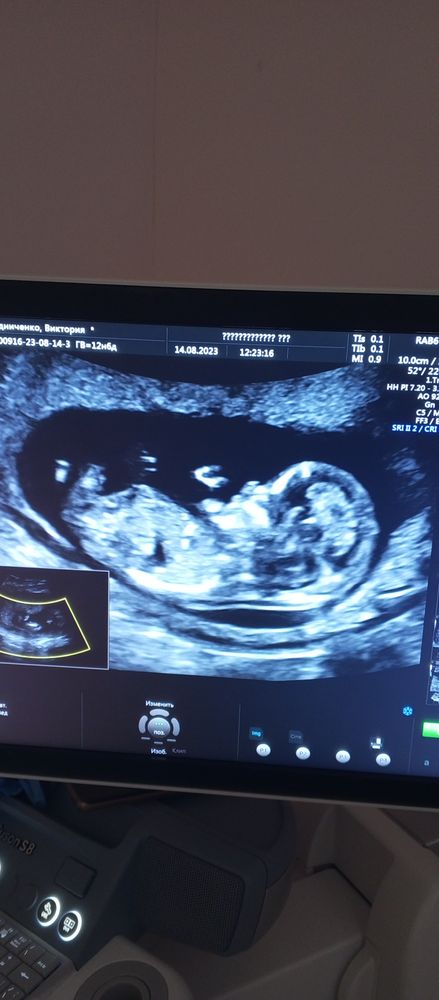

Видела много постов,где по фото писали пол😁можно и я теперь побалуюсь)

P.S.сегодня пришел нипт,это мальчик🎉

В Я здорова вам с вероятностью 98% сказали уже пол. Зачем усложнять. Особенно, если были у Пятых